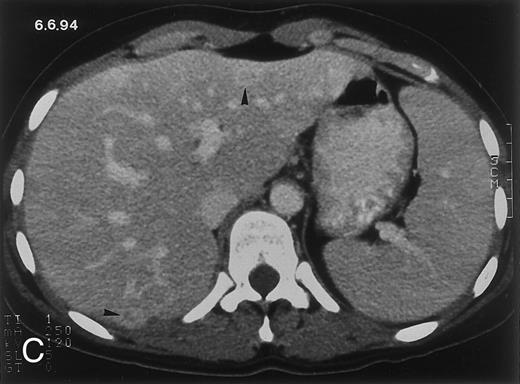

(C) On June 6, 31 days after normalization of neutrophils, CT again shows multiple lesions in the liver (arrowheads) with a different presentation: the small lesions show strong peripheral enhancement. (D) On September 2, 129 days after neutrophil recovery, all hepatic lesions have completely resolved.